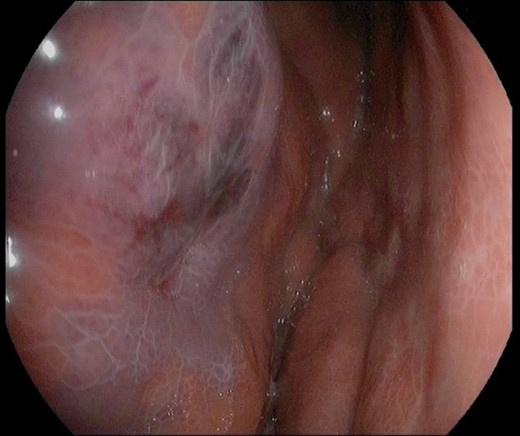

A 45-year-old man presented himself to the emergency department with upper abdominal pain, nausea and vomiting for 3 days. Upon physical examination, the abdomen was tender to palpation but there was no muscle guarding. Laboratory results revealed a high-grade infection, as presented in Table 1. No pneumoperitoneum was seen on the standing chest X-ray. A complementary abdominal CT-scan revealed a widespread thickening of the gastric wall, without signs of perforation (Fig. 1). The patient was admitted and an esophageal-gastro-duodenoscopy revealed diffuse erythema and edema of the gastric wall, suggestive for an acute severe gastritis (Fig. 2). Gastric ischemia or a malignancy, were considered as etiology of the gastritis. H2-blocker and antibiotic therapy with cefuroxime and metronidazole were administered. The next day, the patient deteriorated into a septic shock with multiple organ failure and a high serum lactate (Table 1). A diagnostic laparoscopy was performed. However, due to widespread irreversible gastric ischemia, laparoscopy was converted to a laparotomy (Fig. 3), resulting in a total gastrectomy without primary anastomosis. After surgery the patient was admitted to the intensive care unit for hemodynamic support and continuous veno-venous hemofiltration for multiple organ failure. Because the patient’s condition was considered as unstable, the anastomoses were conducted during a second surgical procedure 2 days after the emergency surgery. During this second surgical procedure a Roux-Y esophagojejunostomy was performed. The overall presentation raised suspicion of streptococcal toxic shock syndrome, causing the multi-organ involvement. This was confirmed when cultures and pathological examination showed a phlegmonous gastritis based on a group A Streptococcus. The patient recovered quickly and 2 weeks after the initial surgery he was discharged.

Peroperative image during laparotomy with dark red and diffuse gastric wall thickening. Some parts of the gastric wall are ischemic and have intact bullae on them.

The localized type is characterized by hyperemia and erosion, ulceration, necrosis or bleeding. The diffuse type is characterized by dark red and diffuse gastric wall thickening, which was present in our case (Fig. 3). This type can cause gastric cavity expansion and gastric wall perforation [10]. The localized type is associated with a lower mortality rate (10%) than the diffuse type (54%) [1, 2].